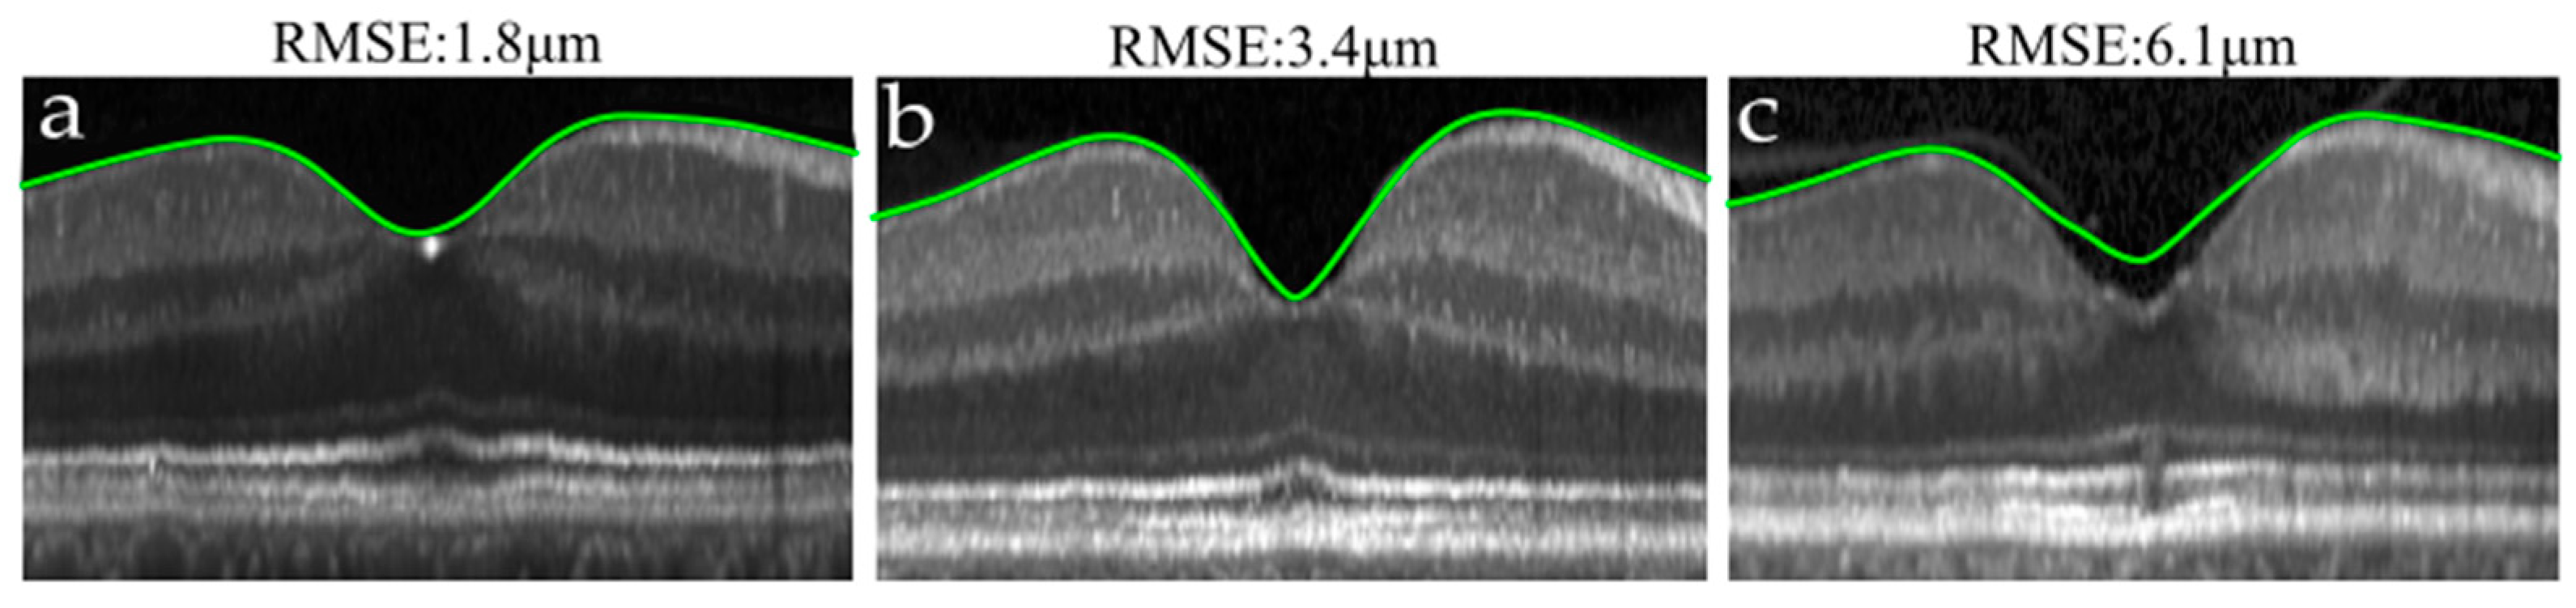

- Fitting error: to measure how well each model adjusted the data. For that, the root mean square error (RMSE) between the TRT maps obtained without using any model () and the TRT maps derived after fitting () was used:where and account for the x and y axes position in the grid, and refers to the number of points in each grid direction.

3.2. Foveal Pit Mathematical Modelling